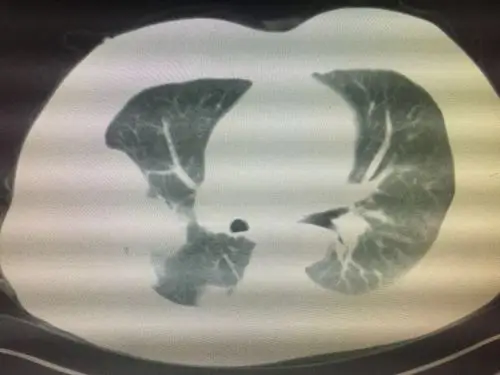

肺包虫囊肿

肺内包虫